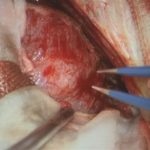

術中写真

摘出 前

摘出 中

摘出 後